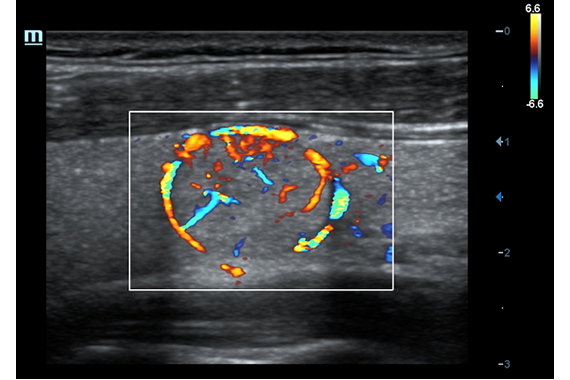

• HR Flow - режим отображения кровотока с высоким временным и пространственным разрешением для точной и однородной визуализации сосудов, в том числе самых мелких.

Энергетический допплер:

Да

Цветовой допплер:

• HR Flow - режим отображения кровотока с высоким временным и пространственным разрешением для точной и однородной визуализации сосудов, в том числе самых мелких